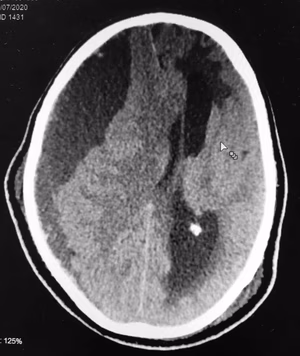

O papel do Neurocirurgião na estenose de carótida e AVC.

O papel do Neurocirurgião no AVC isquêmico.